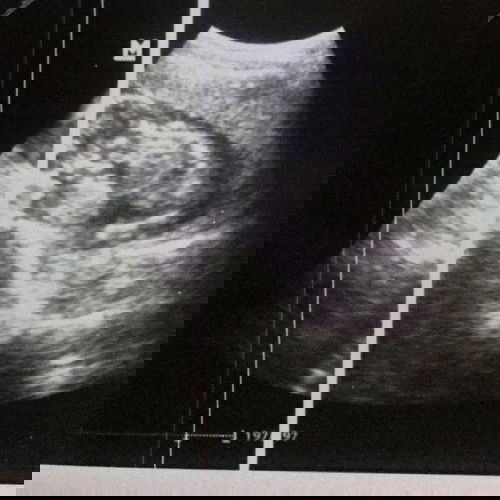

Saya hamil 38 w 6 d, posisi bayi sungsang dan sudah disarankan sc sama bidan. Sebenarnya jika sudah disarankan sc itu nunggu kontraksi atau nggak sih bun? Soalnya saya baca2 yg lain katanya jangan nunggu kontraksi nnti sakitnya 2x. Tapi tadi kata bidanku suruh nunggu kontraksi dan suruh nunggu hpl nya. Saya bingung bun. Kemarin saya disuruh balik tgl 5 ini tetapi skarang malah suruh nunggu hpl nya tgl 13 dan biar kontraksi dulu. #firstmom #pleasehelp